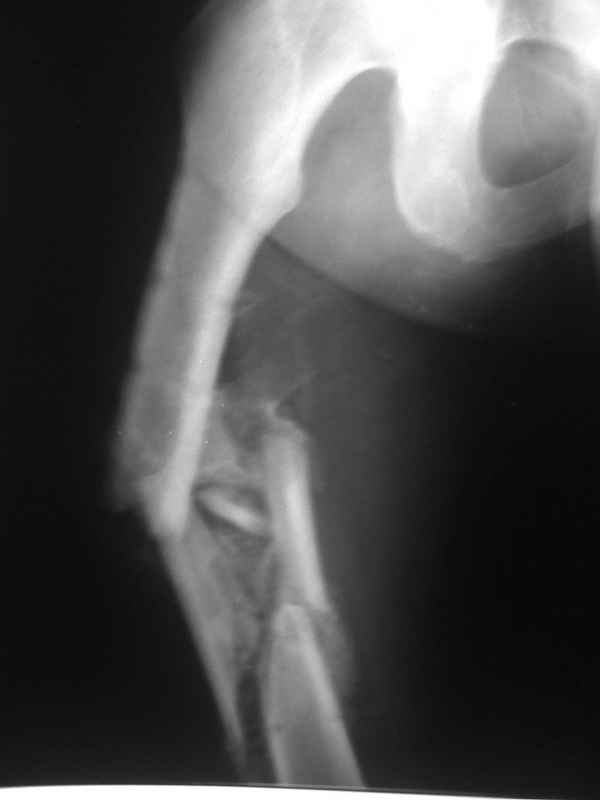

Вы думаете, что в данной ситуации возможна закрытая мобилизация?

Попробовать-то можно. И просто руками "об колено", а то и наложить аппарат, приложить флексионные и ротационые усилия прямо за разъединенные секции.

Если уж никак, то сделать чрескожную остеотомию.

Но если картинки недавние, IMHO должно получиться закрыто разобщить.